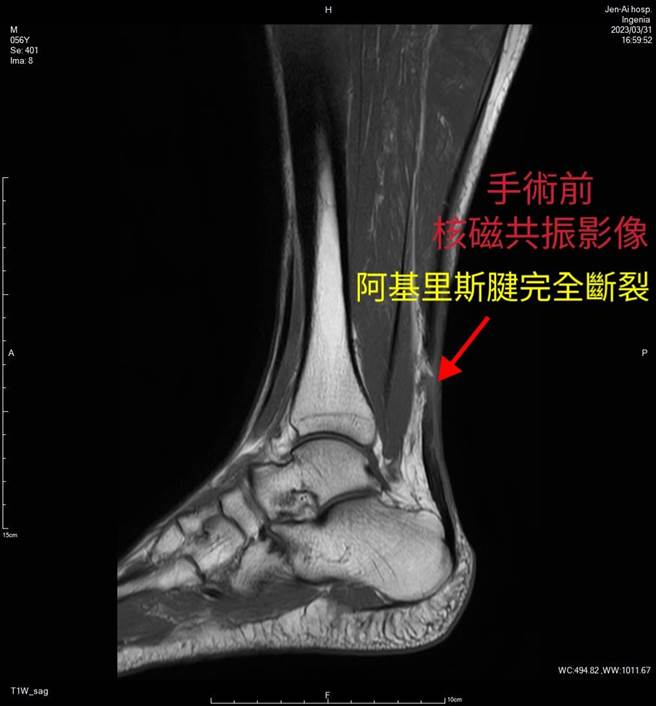

42岁王姓男子近期在羽毛球比赛中跳跃击球,未料落地后「啪」一声,右脚跟出现剧痛,几乎无法行走,立即就医发现竟是右脚「阿基里斯腱」断裂,经过「内视镜微创阿基里斯腱修补手术」治疗,加上3个月调整式踝护具保护和復健,王先生现已可以重返球场。